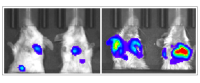

Gu and his colleagues fed mice either a carbohydrate-free ketogenic diet or control diet for 7 weeks, tracking the size and weight of their primary tumors. As expected, they observed a noticeable reduction in primary tumor growth in the ketogenic group compared to the control group. However, fluorescence imaging of the lungs revealed that mice on the ketogenic diet had accumulated a much larger number of metastatic nodules.

In vivo luminescence imaging of lung tumors (metastasized from breast cancer) in mouse models, comparing the keto diet (right image) and the control (left image).